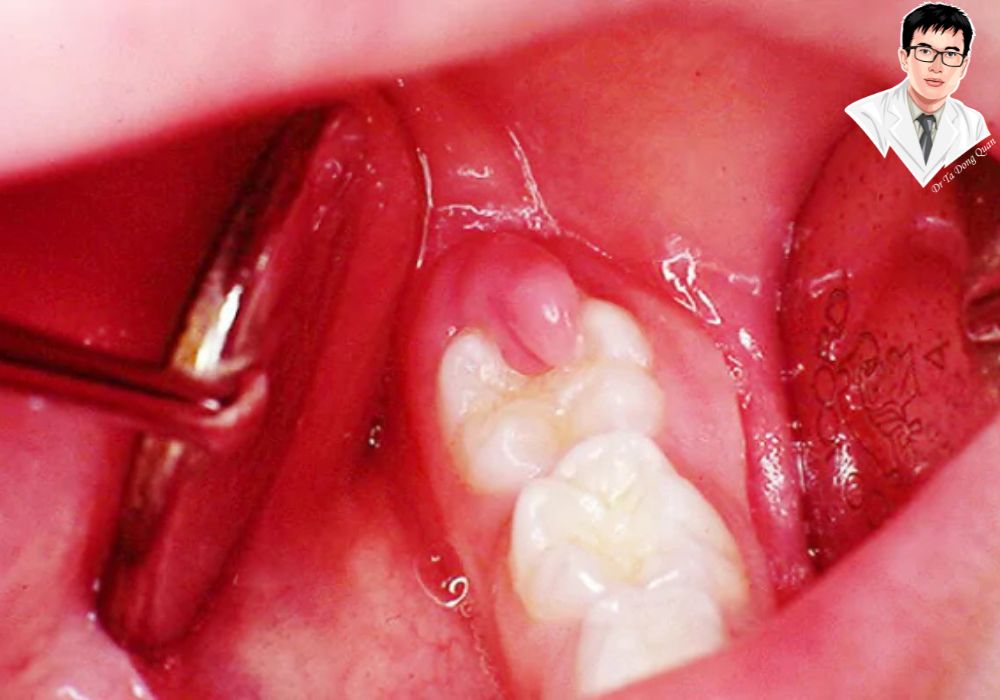

Phương pháp này sử dụng dao phẫu thuật nhỏ để loại bỏ phần lợi thừa bao phủ răng khôn. Khi thực hiện cắt lợi trùm bằng dao tiểu phẫu, bác sĩ gây tê tại chỗ giúp bạn không cảm thấy đau. Quá trình cắt lợi trùm có thể kèm chảy máu nhẹ nhưng thường được kiểm soát tốt. Phương pháp này đã được áp dụng lâu đời và vẫn mang lại hiệu quả cao nếu chăm sóc đúng cách.

Thực hiện cắt lợi trùm an toàn, nhanh chóng

Quy trình cắt lợi trùm thường bắt đầu bằng gây tê tại chỗ giúp bạn không đau trong suốt quá trình. Sau đó, bác sĩ dùng dao tiểu phẫu hoặc laser để loại bỏ phần lợi thừa. Cuối cùng, cầm máu và khâu vết thương nếu cần. Thời gian thực hiện thường kéo dài từ 15 đến 30 phút.